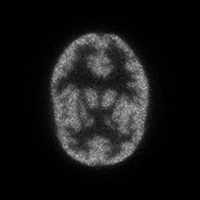

For PET reconstruction a fly is a 3D point that emits annihilations. Using a cooperative co-evolution scheme to optimise the position of annihilation sites, the population of flies evolves so that the data estimated from flies matches measured data. The final population approximates the radioactivity concentration (see Figure 5 for examples). This approach showed promising results in relatively simple test cases in fully-3D LOR space [15,16,17,18,19]. However, the test data did not take into account physical phenomena such as the mean free path of positrons, the non-collinarity of annihilation photons, the γ-ray attenuation, and the Compton scattering.

| (a) Cardiac example, reference image. | (b) Cardiac example, reconstructed data. | (c) Hoffman phantom, reference image. | (d) Hoffman phantom, reconstructed data. |

Figure 5: Tomographic reconstruction using my cooperative co-evolution scheme dedicated to PET.